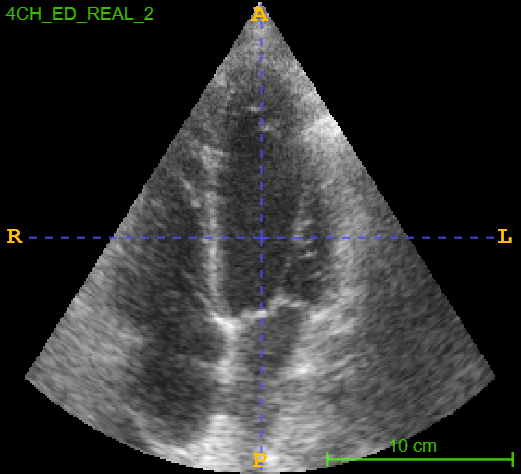

4.3 CAMUS Echocardiogram View Classification

After investigating the issue of synthetic simplicity in the digit classification task, we demonstrate the phenomenon on a representative medical imaging task of cardiac view classification from echocardiographs. We utilized the publicly available echocardiography dataset "Cardiac Acquisitions for Multi-structure Ultrasound Segmentation" (CAMUS) [8] for this experiment. The CAMUS dataset comprises four types of cardiac views from over 500 subjects: two-chamber end-systolic (2CH ES), two-chamber end-diastolic (2CH ED), four-chamber end-systolic (4CH ES), and four-chamber end-diastolic (4CH ED). We focused on the "4CH ED" and "2CH ED" classes in the CAMUS dataset for classification task. Figure 2 shows real and synthetic samples of 4CH ED and 2CH ED echocardiogram views.